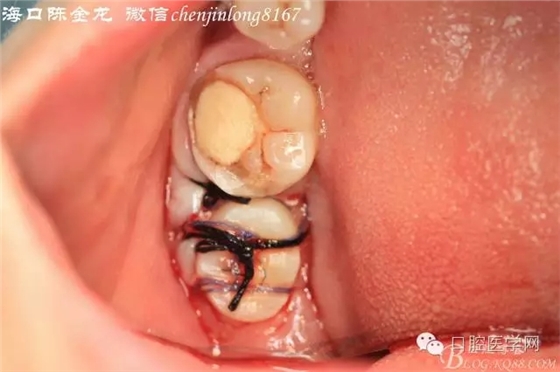

右上8供體牙

右下8被移植牙

右下8形態(tài)

右上8修整根尖后形態(tài)

拔牙窩預備移植后,縫合固定

咬合無干擾